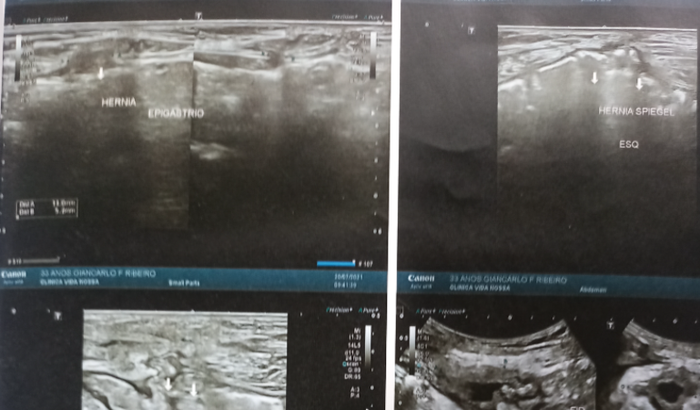

Eu me chamo Giancarlo,tenho 35 anos. Faz 3 anos que venho passando por cirurgias,ja fiz de colostomia 3 vezes,usei bolsa por 2 anos,agora faz 1 ano e quase 5 meses novamente aguardando cirurgia devido a 8 hérnias que surgiram nesse tempo.